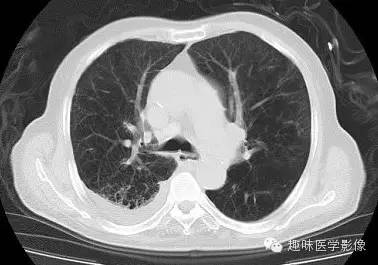

【病例】肺脓肿1例CT影像特点

[影像描述]

双肺多发无壁低密度区,以右肺下叶底部为主。右肺下叶见大片不规则实变阴影伴多发空洞影,实变肺组织内见支气管气象,右肺下叶支气管局部显示不清。纵隔内见淋巴结。右侧胸腔内见积液影,邻近胸膜肥厚。主动脉、冠状动脉钙化。

右肺下叶肺脓肿、肺炎伴胸腔积液,肺气肿、肺大泡。

右胸廓变小,心影右移;右肺下叶多房性空洞,空洞内未见明显液平面,右下肺病变应该是下叶阻塞性肺炎,实变肺组织内见支气管气像,邻近胸膜增厚,并合并胸腔积液,支持肺脓肿。